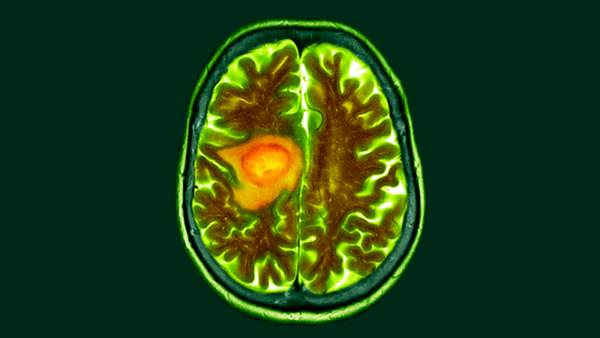

Віруси ВПЛ можуть спричиняти рак шийки матки та інші види раку.